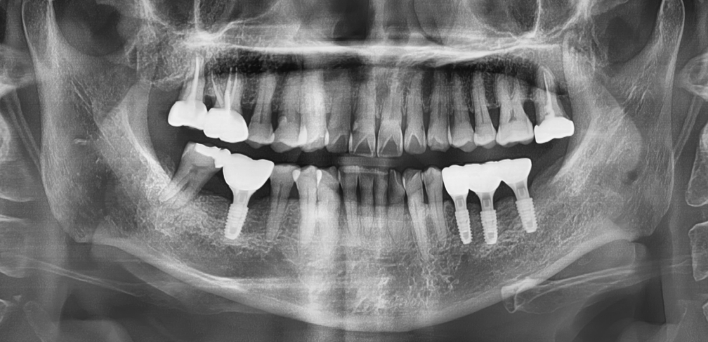

After After

2020.02.30

위, 아래 6개씩 식립

디지털 풀아치 임플란트

임플란트 Before & After